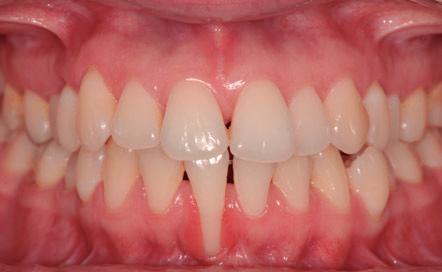

En la foto de sonrisa (Figura 2, derecha), observamos unos márgenes gingivales desnivelados y triángulos negros entre los incisivos superiores, debidos a la inclinación o tipo distal excesivo y a la forma triangular de los incisivos. En la foto intraoral, observamos una gran recesión gingival a nivel del 4.1 (Figura 2, izquierda).

Fig.2. Foto de sonrisa, llama la atención el triángulo negro entre 1.1 y 2.1 (izquierda). Foto intraoral frontal, destaca la recesión gingival del 4.1 (derecha).

El 4.1 presenta una recesión gingival avanzada debido a la posición de la raíz en relación a una cresta estrecha y un periodonto fino (Fig. 2).